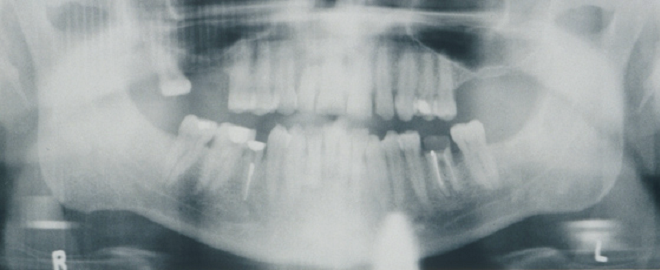

Panoramic imaging shows the root canal in teeth 29 and 30 and endodontic therapy in teeth 19 and 29. Tooth 19 has crown breakdown and inadequate fill. Teeth 2 and 3 are missing (Figure 2, left). The findings on MRI and CT imaging were normal.